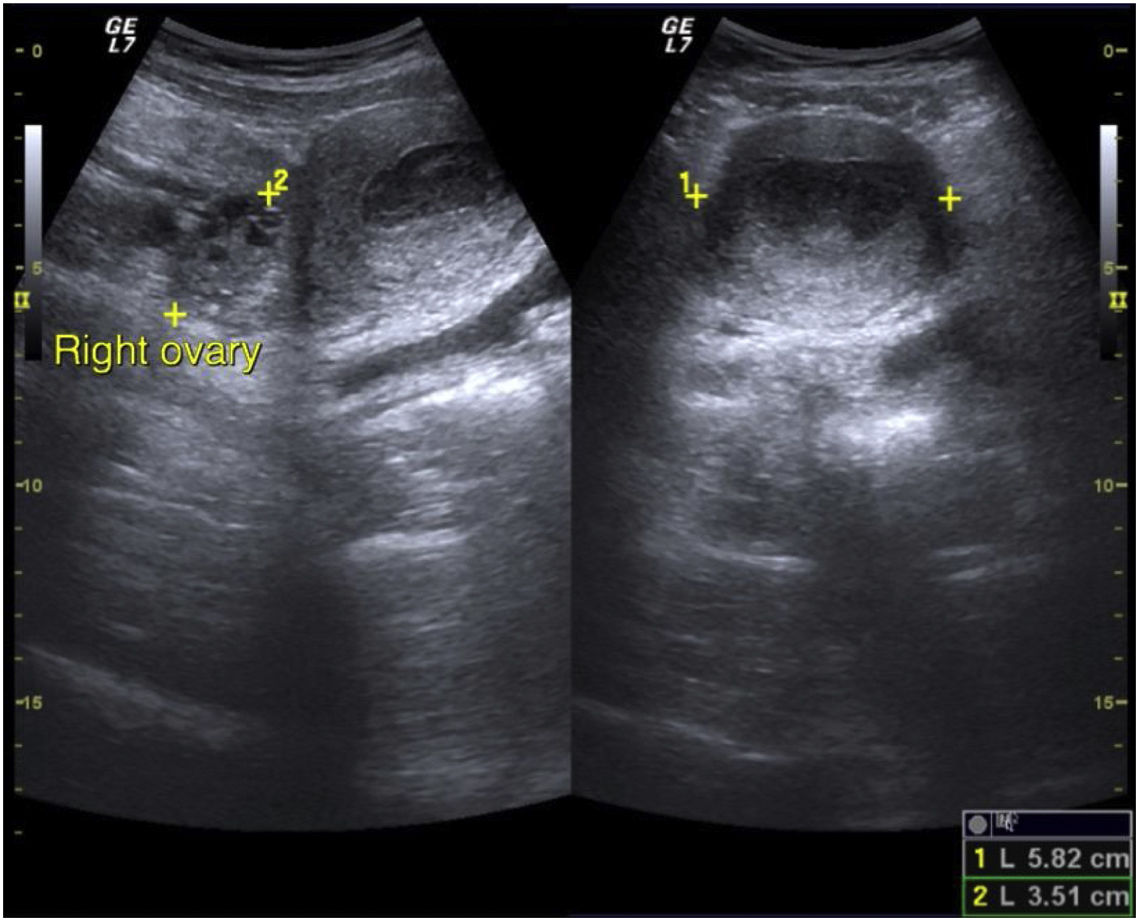

Datos clínicosNiña de 12 años de edad con cuatro episodios de dolor abdominal en los últimos 4 meses.

Pregunta 1Describa los hallazgos radiológicos.

(Pregunta de texto libre, no se proporciona opción de respuesta.)